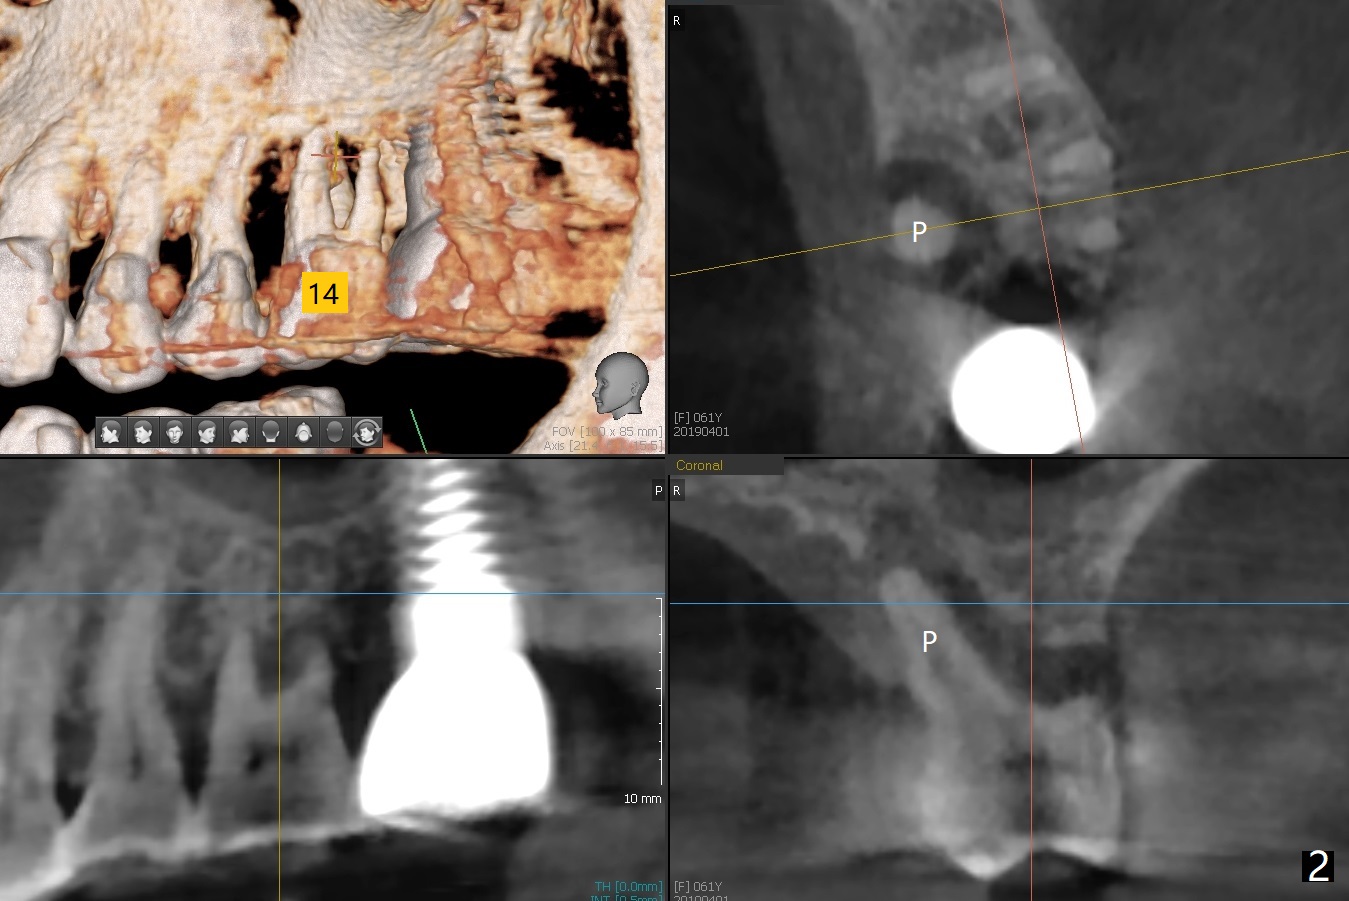

A 61-year-old woman requests implant at #14 because of mobility after exfolia-tion of the tooth #18 (Fig.1). Because of severe bone loss, especially palatal (Fig.2,3 P), osteotomy will be initiated with guide as buccal as possible (Fig.4). To reduce abutment screw loosening, a 5x11 mm tissue-level implant will be placed (Fig.5 blue (pink: abut-ment)).